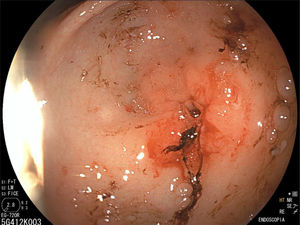

La endoscopia reveló un estrechamiento del píloro que impedía el paso del endoscopio al duodeno (fig. 1), por lo que se realizó dilatación hidroneumática con balón (figs. 2 y 3). Las biopsias informaron gastritis asociada a Helicobacter pylori e hiperplasia foveolar.